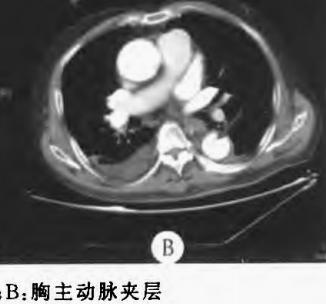

动脉夹层是急症中的急症,随时有生命危险,增强CT诊断动脉夹层一般不难。主动脉夹层常表现为突发的剧烈胸背或腹部撕裂样疼痛,常伴血压升高,但是部分患者症状不典型,甚至没有疼痛感,掌握CT平扫对动脉夹层的诊断价值,有时候可尽早发现潜在的巨大危险!

图1

火眼金睛的小伙伴可能发现了,主动脉有问题,动脉破裂了?

图2

然而,先冷静!这个阴影是半月形的略高密度阴影,是片状的,是不均匀的,这个是伪影!增强扫描,主动脉很正常!